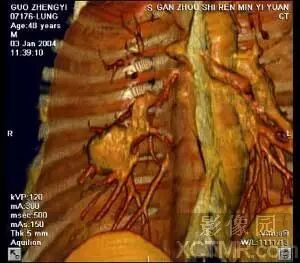

IVR图象显示支气管与肺部肿瘤之间的关系,此病例虽然没有进行增强,

但是通过图象后处理仍然清晰地 显示出肺内支气管及肿瘤组织,并且可以看到肿瘤支气管关系密切。